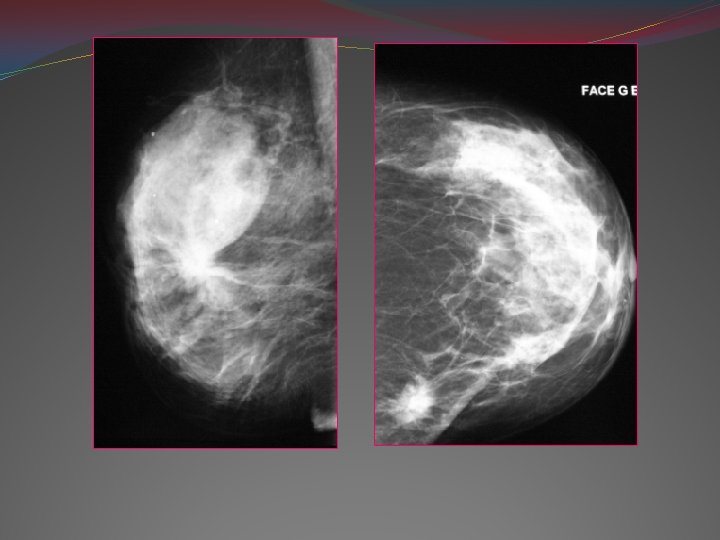

Moyens d’imagerie 1 -Mammographie: -Examen de référence: diagnostic, dépistage -1ère partie du cycle TECHNIQUE: Exploration toujours bilatérale, compression Incidences standards: face, profil, oblique

�Incidence de face: Critères de réussite: Sein au centre du film Mamelon vers l’avt Pectoral visible Graisse rétro glandulaire visible

�Incidence de profil Critères de qualité Sillon sous mammaire visible Pectoral en bordure du film Mamelon visible

�Incidence oblique externe: Critères de réussite: Pectoral++ Sillon sous mammaire est visible Bande graisseuse rétro glandulaire visible

1 - NODULE MAMMAIRE: Mammo: v image stellaire: - Traduction la plus classique de cancer - Étoile blanche: traduction classique du CCI centre dense: plage de tumeur + nécrose périphérie: spicules la fibrose du stroma Halo: zone radio transparente autour de l’opacité: contingent graisseux déshydraté

vopacité: Forme: arrondie, ovalaire aspect trompeur Contours: flous, irréguliers, lobulé (KC médullaire, colloïde, sarcome, métastase) +/- halo clair péri lésionnel autres éléments; clinique, écho

v. Autres signes associés: Discordance de la taille mammo/clinique Épaississement ou rétraction cutanée (signe de la tente) ou mamelonnaire

Signe de la tente Clichés en MLO, lecture en miroir: asymétrie de densité Cliché CC: signe de la tente avec au sommet une opacité